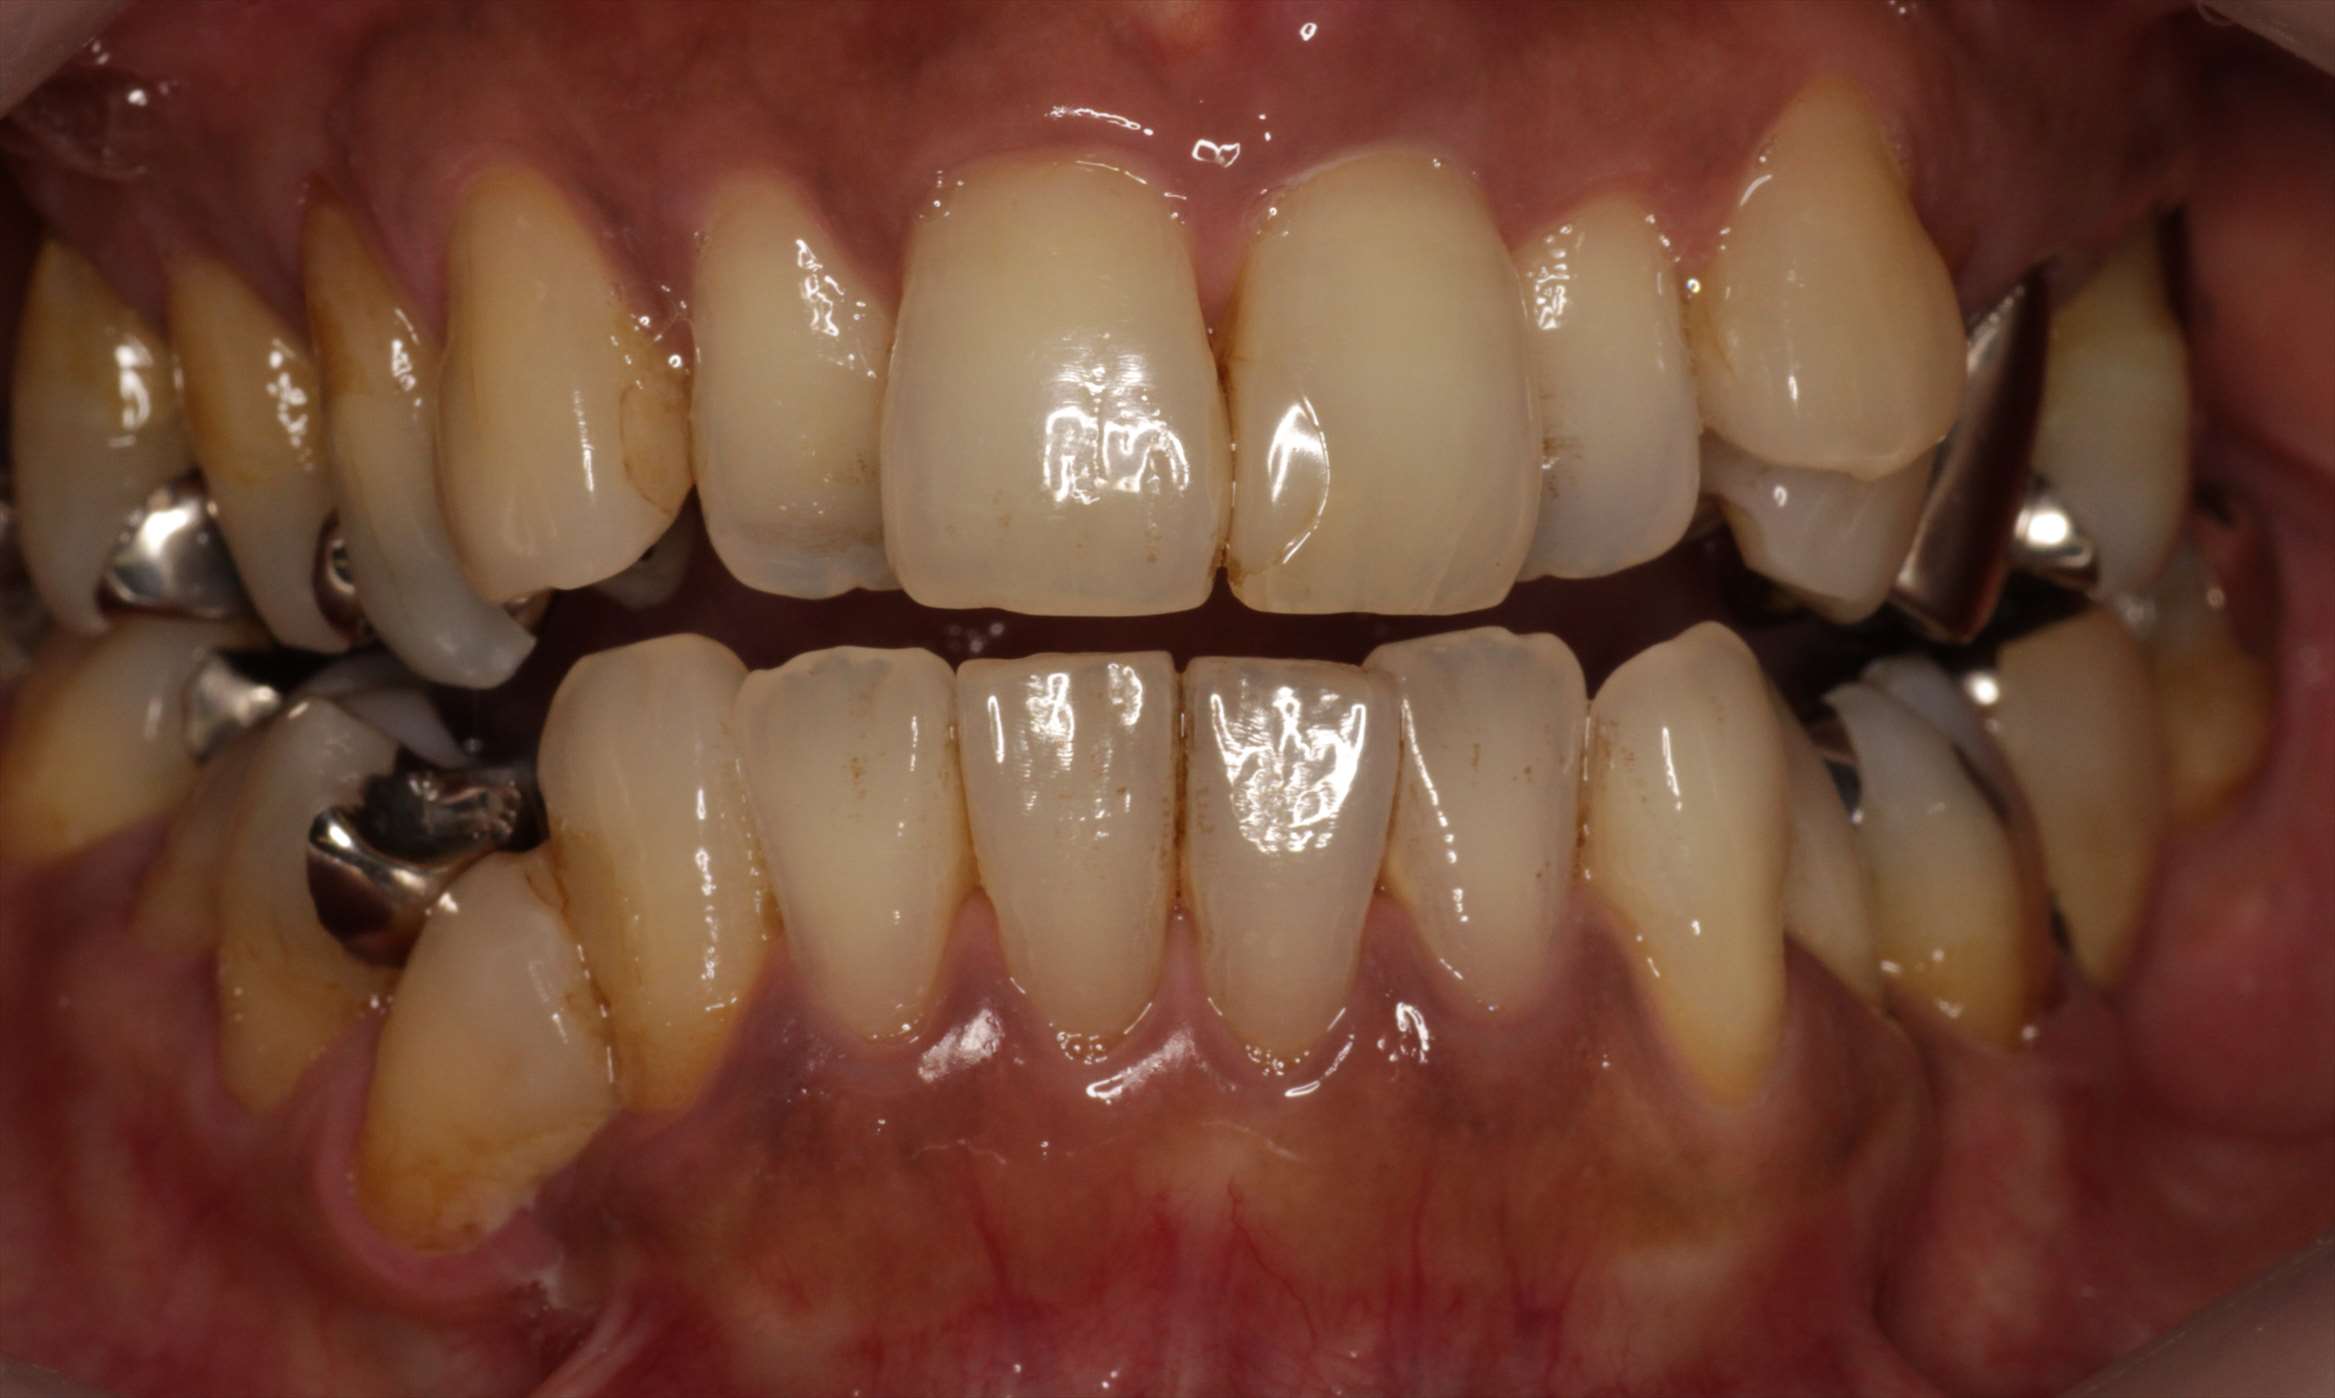

- 治療前